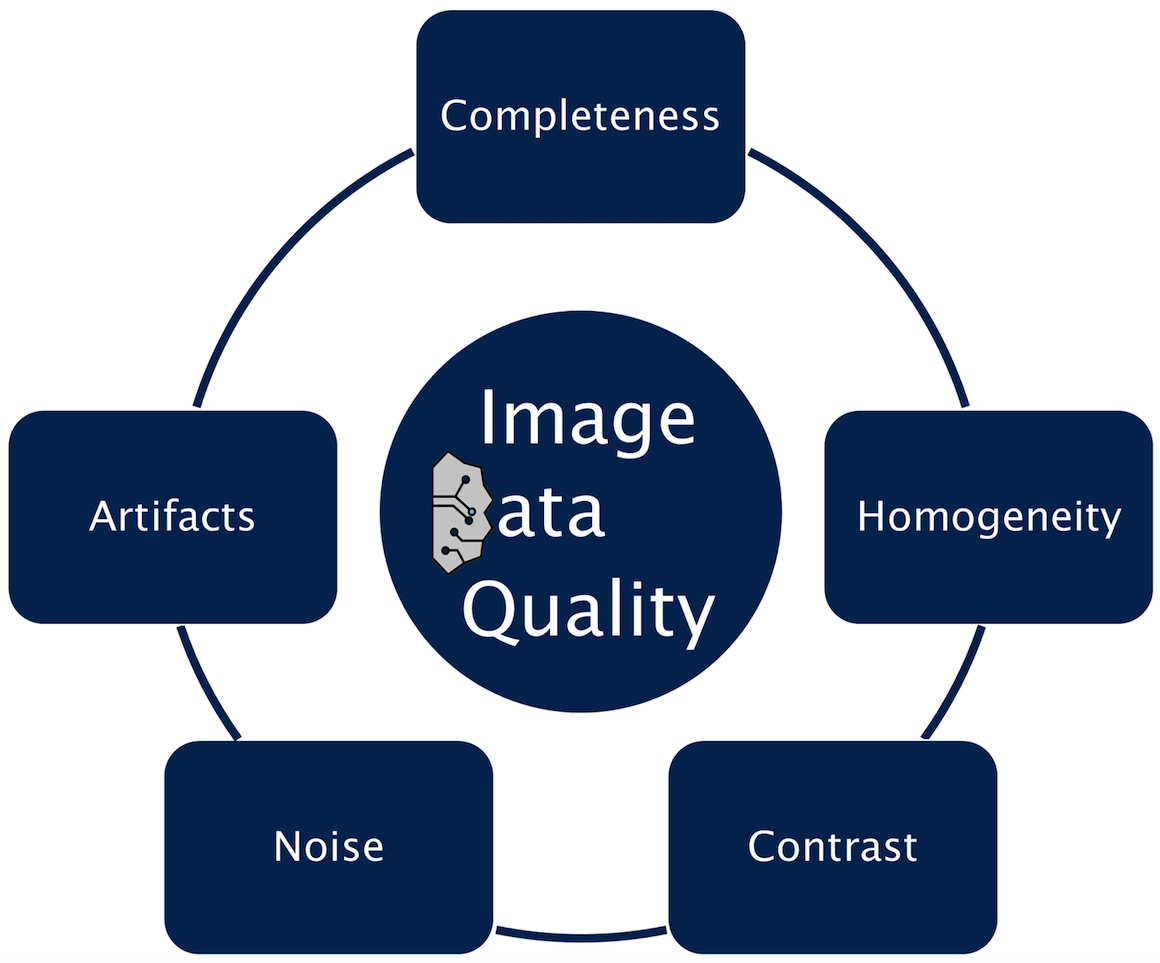

The MedDigit team pursues the goal of a continuous registration and quantitative analysis of brain structure and function of all patients with neurological and neuropsychiatric disorders in Saxony-Anhalt. The team develops a fully automated digital system for processing clinical brain data from the Department of Neurology and external caregivers (MRI/MEG/EEG) as well as for deriving biomarkers for defined neurological disorders. The system comprises components for ensuring comparability of data that were acquired in a non-standardized way, for the automated digital analysis and enhancement of data quality, the automated feature extraction and data classification as well as the determination of clinically relevant, quantitative biomarkers.